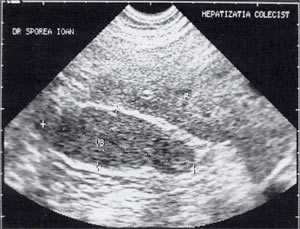

В исследовании, проведенном в США, "желчный сладж" выглядел в виде гиперэхогенного образования в желчном пузыре с горизонтальным уровнем без задней тени, форма которого медленно изменялась при движении больного [10]. Характерный признак "желчного сладжа" - изменение его вида на сканограмме в зависимости от изменения положения тела больного и медленным достижением нового горизонтального уровеня. Общим правилом является отсутствие дистальной акустической тени. Эхогенность сладжа может быть различной. Иногда сладж заполняет весь желчный пузырь, затрудняя дифференцировку между тканью печени и желчным пузырем. Эта ситуация называется "гепатизация желчного пузыря" (рис. 1).

Рис. 1. Гепатизация желчного пузыря, полностью заполненного сладжем.